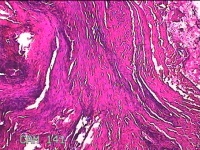

右耳前瘘管

性别

男

年龄

53岁

临床诊断

一般病史

反复右耳前红肿、流脓2月。

标本名称

大体所见

灰白暗红色组织.3x0.8x0.3cm一块,表面糜烂,切面灰白暗红色,质中。